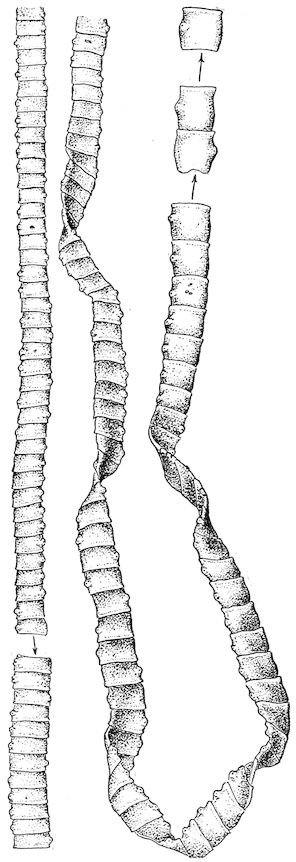

Fig. 10.—Dressing for fracture of the horn.